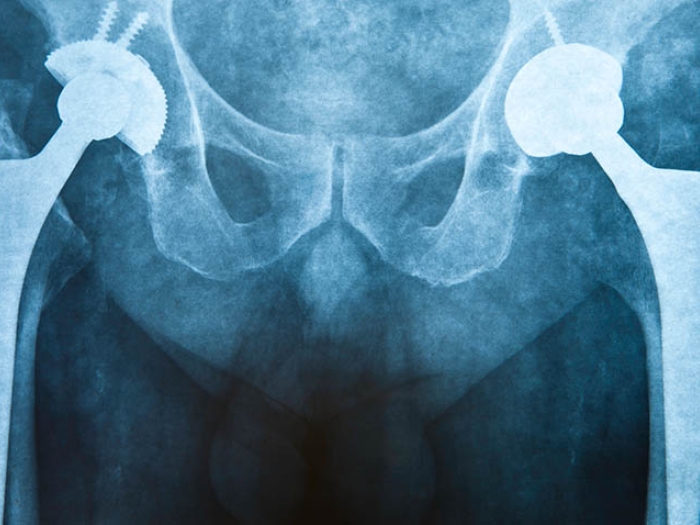

x-ray of hips

Abnormal Bone Formation After Trauma Explained and Reversed in Mice

Heterotopic ossification (HO) is a form of abnormal healing typified by bone forming within muscle or soft tissue as the body heals from injury or surgery. Historically, there has been no treatment for HO, but new research suggests that could change.